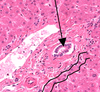

Islet of langerhans

indicates you are in the pancreas

endocrine gland

what is this? What is secreted here?

Islet of langerhans

a cell -> glucagon

b cell -> insulin

∂ cell -> somatostatin

F or PP cell -> pancreas polypeptide

what is the gland around the “island” in the middle? what type of gland is this?

exocrine pancreas around the islet of langerhans

acini cells are stained bright red

compound acinar gland

what is red? blue (in the pancreas)

red – centroacinar cell – pale staining

blue – serous acinus cell

what is this in the panceas

centroacinar cells

pale staining little round ducts